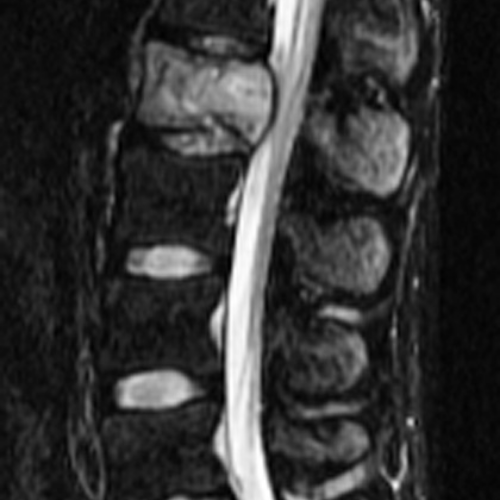

Tanı aşamasında en güçlü araç kontrastlı MR (Emar) görüntülemesidir. Kemik yapının detaylı incelenmesi için Bilgisayarlı Tomografi (BT) ve tümörün yayılımını belirlemek için PET/CT gibi yöntemler kullanılır. Kesin teşhis ise genellikle doku örneği (biyopsi) ile konulur.

Tedavi yaklaşımı; tümörün tipine, büyüklüğüne, konumuna ve hastanın genel sağlık durumuna göre multidisipliner bir ekip (beyin cerrahı, onkolog, radyolog) tarafından belirlenir. İyi huylu (benign) tümörlerde sadece cerrahi çıkarma yeterli olabilirken, kötü huylu (malign) tümörlerde cerrahiye ek olarak radyoterapi ve kemoterapi uygulanır. Günümüzde "Stereotaktik Radyocerrahi" (CyberKnife gibi) yöntemleri, cerrahinin riskli olduğu bölgelerdeki tümörlere yüksek dozda radyasyonu hassas bir şekilde odaklayarak başarılı sonuçlar vermektedir.